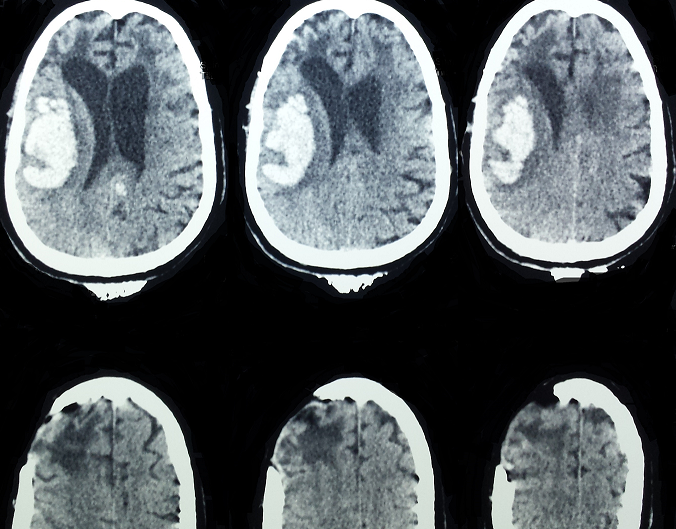

Spontaneous intracerebral hemorrhage (ICH) accounts for 15% of stroke cases in the US and Europe and up to 30% in Asian populations. Intracerebral hemorrhage is a relatively uncommon form of stroke-it causes only 10 to 15 percent of all strokes. It is more disabling and has a higher mortality rate than ischemic stroke, and it can occur at any age. It is slightly more common in men than in women. Its etiologies are dominated by hypertension, arteriovenous malformation, aneurysmal rupture, cerebral amyloid angiopathy, intracranial neoplasm and coagulopathy. We report the first case to date of spontaneous intracerebral hemorrhage associated with polyglobulia. A 56-years-old man, with history of polyglobulia and spontaneous intracerebral hemorrhage treated surgically in 2011, was admitted to the emergency service with the complaint of headache, disturbance of consciousness. Clinical examination is estimated GCS 13/15 and 2/5 left hemiparesis. An emergency CT-scan revealed a recurrent parieto-temporal hematoma, sequelar frontal hypodensity of the old stroke with its cranial flap.